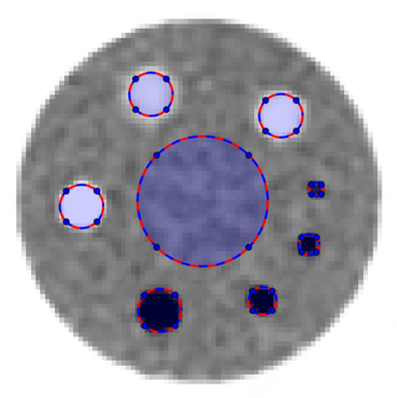

a)

b)

Two numerical 2D phantoms shown in Fig. 1 were used in simulations. The brain phantom [30] was obtained from a high quality clinical PET image. The uniform phantom consists of 4 uniform hot spheres and 2 uniform cold spheres with distinct radii: 4, 6, 8 (cold), 10 (cold), 12, 14 pixels. The contrast ratio for the cold and hot spheres are and , respectively. All simulations were performed in a 64-bit Windows 10 OS laptop with Intel Core i7-8550U Processor at 1.80 GHz, 16 GB of DDR4 memory and 512 GB SATA SSD.